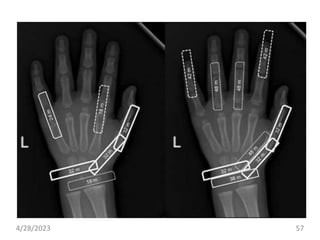

C. Bone Age

• evaluate growth and maturity and to diagnose and

manage pediatric disorders.

• For 1-8 yrs, bone age is determined by examining

carpal bones in X-ray of left wrist.

• No. of osification centres in wrist = Age(yrs)+1

Age X-ray

New born Knee, Ankle

3-9 months Shoulder

3 yrs Wrist

12-16 yrs Elbow, Hip

4/28/2023 56

• #57 pediatric endocrinology but also in orthodontics and pediatric orthopedics. because the hand and wrist possess many bones and taking radiographs of the hand and wrist is easy. One reason is that most people are right-handed, and therefore, the right hand is more likely to be injured than the left hand (1). Another reason is that it was determined that physical measurements should be performed on the left side rather than the right side of the body at the conferences of physical anthropologists in the early 1900s

• #58 The hand and wrist bones consist of the radius, ulna, 19 short bones (5 metacarpals and 14 phalanges) and 7 carpals. Bones are formed by endochondral ossification in the radius, ulna and short bones and by intramembranous ossification in the carpal bones. The maturation rates of the carpals vary among individuals. The completion of maturation occurs earlier in the carpals compared with the long and short bones, and intramembranous ossification is less dependent on GH than endochondral ossification. Therefore, the carpals are not suitable for bone age assessment.